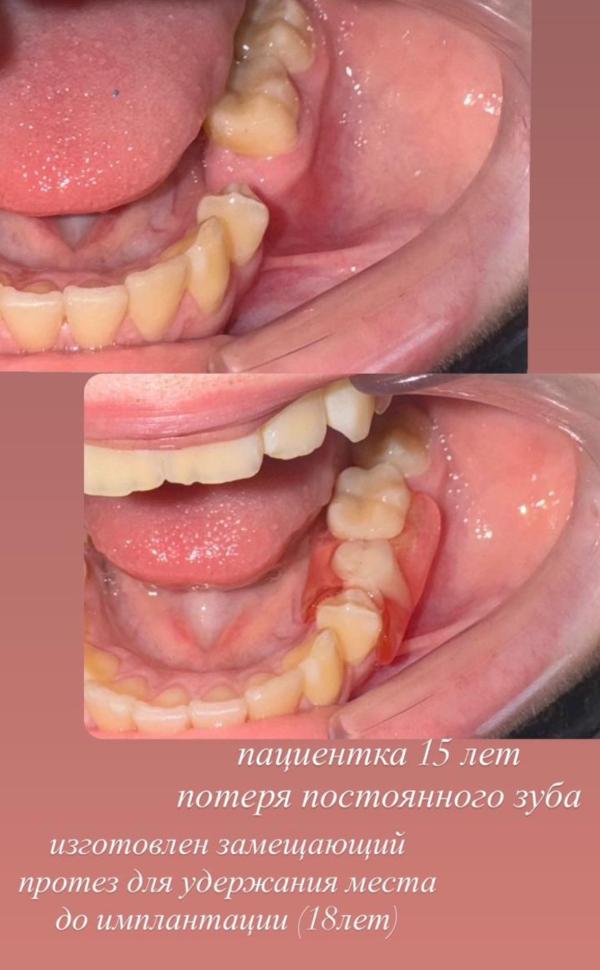

Удерживать место после удаления❗️

А что делать если удалили коренной молочный зуб а постоянного не будет так как частичная адентия (?

В таких случаях изготавливаем съемные пластинки с зубами, 1. будет удерживать место, 2.ребенок полноценно и эффективно будет жевать, 3. стимуляция роста постоянных зубов